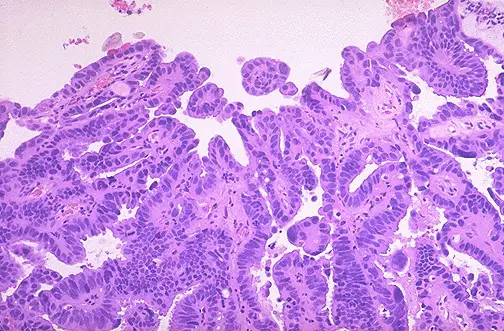

La microfotografía muestra un adenocarcinoma endometrial moderadamente differentiado, ya que se discierne claramente la estructura glandular